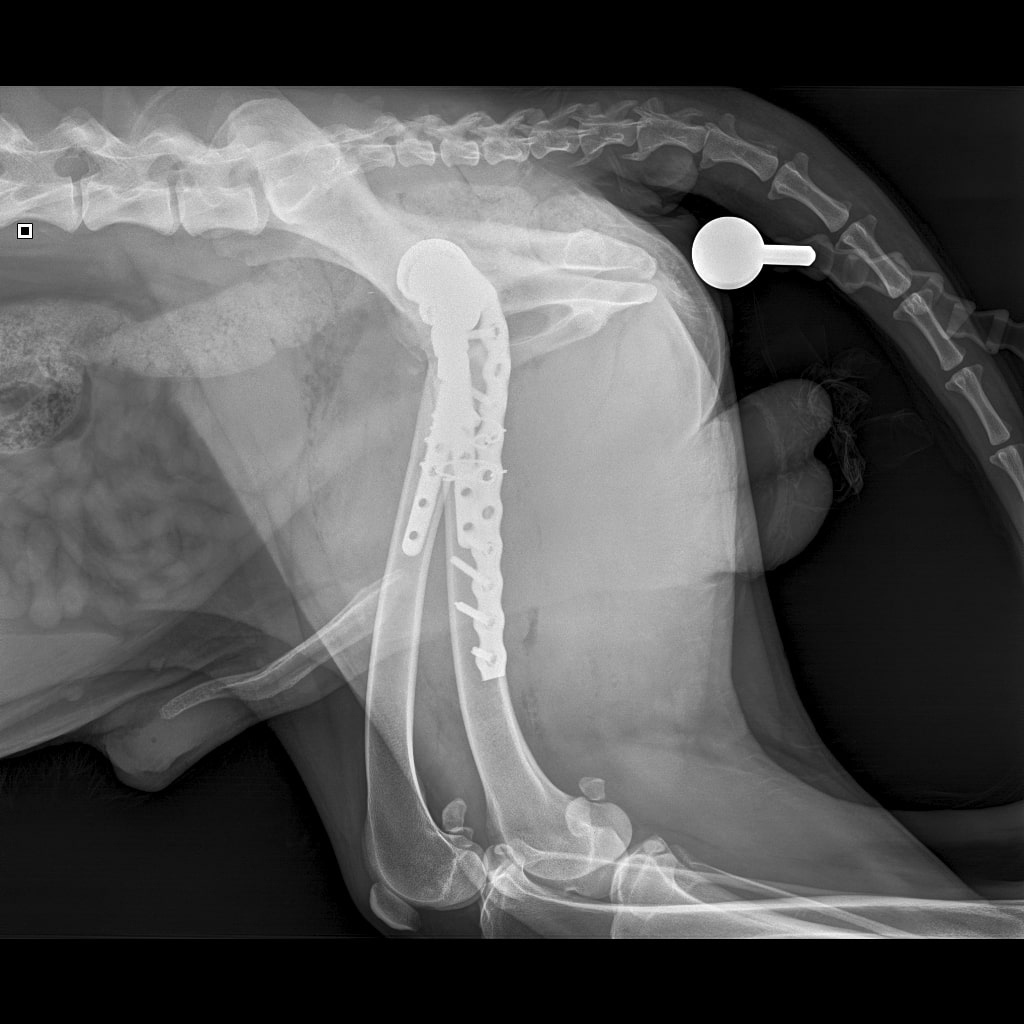

F37B4905-A77F-43B7-A3A7-4AAD9E739F82.jpeg

E6A744CC-768F-480D-8917-7FDAD53F05BD.jpeg

DA1A1524-BA63-434B-95BE-C121F7D5334F.jpeg

4D4A6426-4FE5-4417-ACCB-6DE53B57B90E.jpeg

E358D56E-67BF-4D4C-B3F0-BF8F4089D7A2.jpeg

767DD36C-E2E2-41FB-9CCF-6940421D2BB2.jpeg

701487DA-D6D9-4CE0-B18B-EEB120E78EF2.jpeg

Мы ничего не оплачивали. Все включено.

За время противовоспалительной терапии снизилось воспаление и в левом тазобедренном суставе, но увы, форма головки бедренной кости и состояние шейки бедра , лучше не стали:(((

Операция однозначно нужна.

Снимки столь качественные, что их можно в учебник